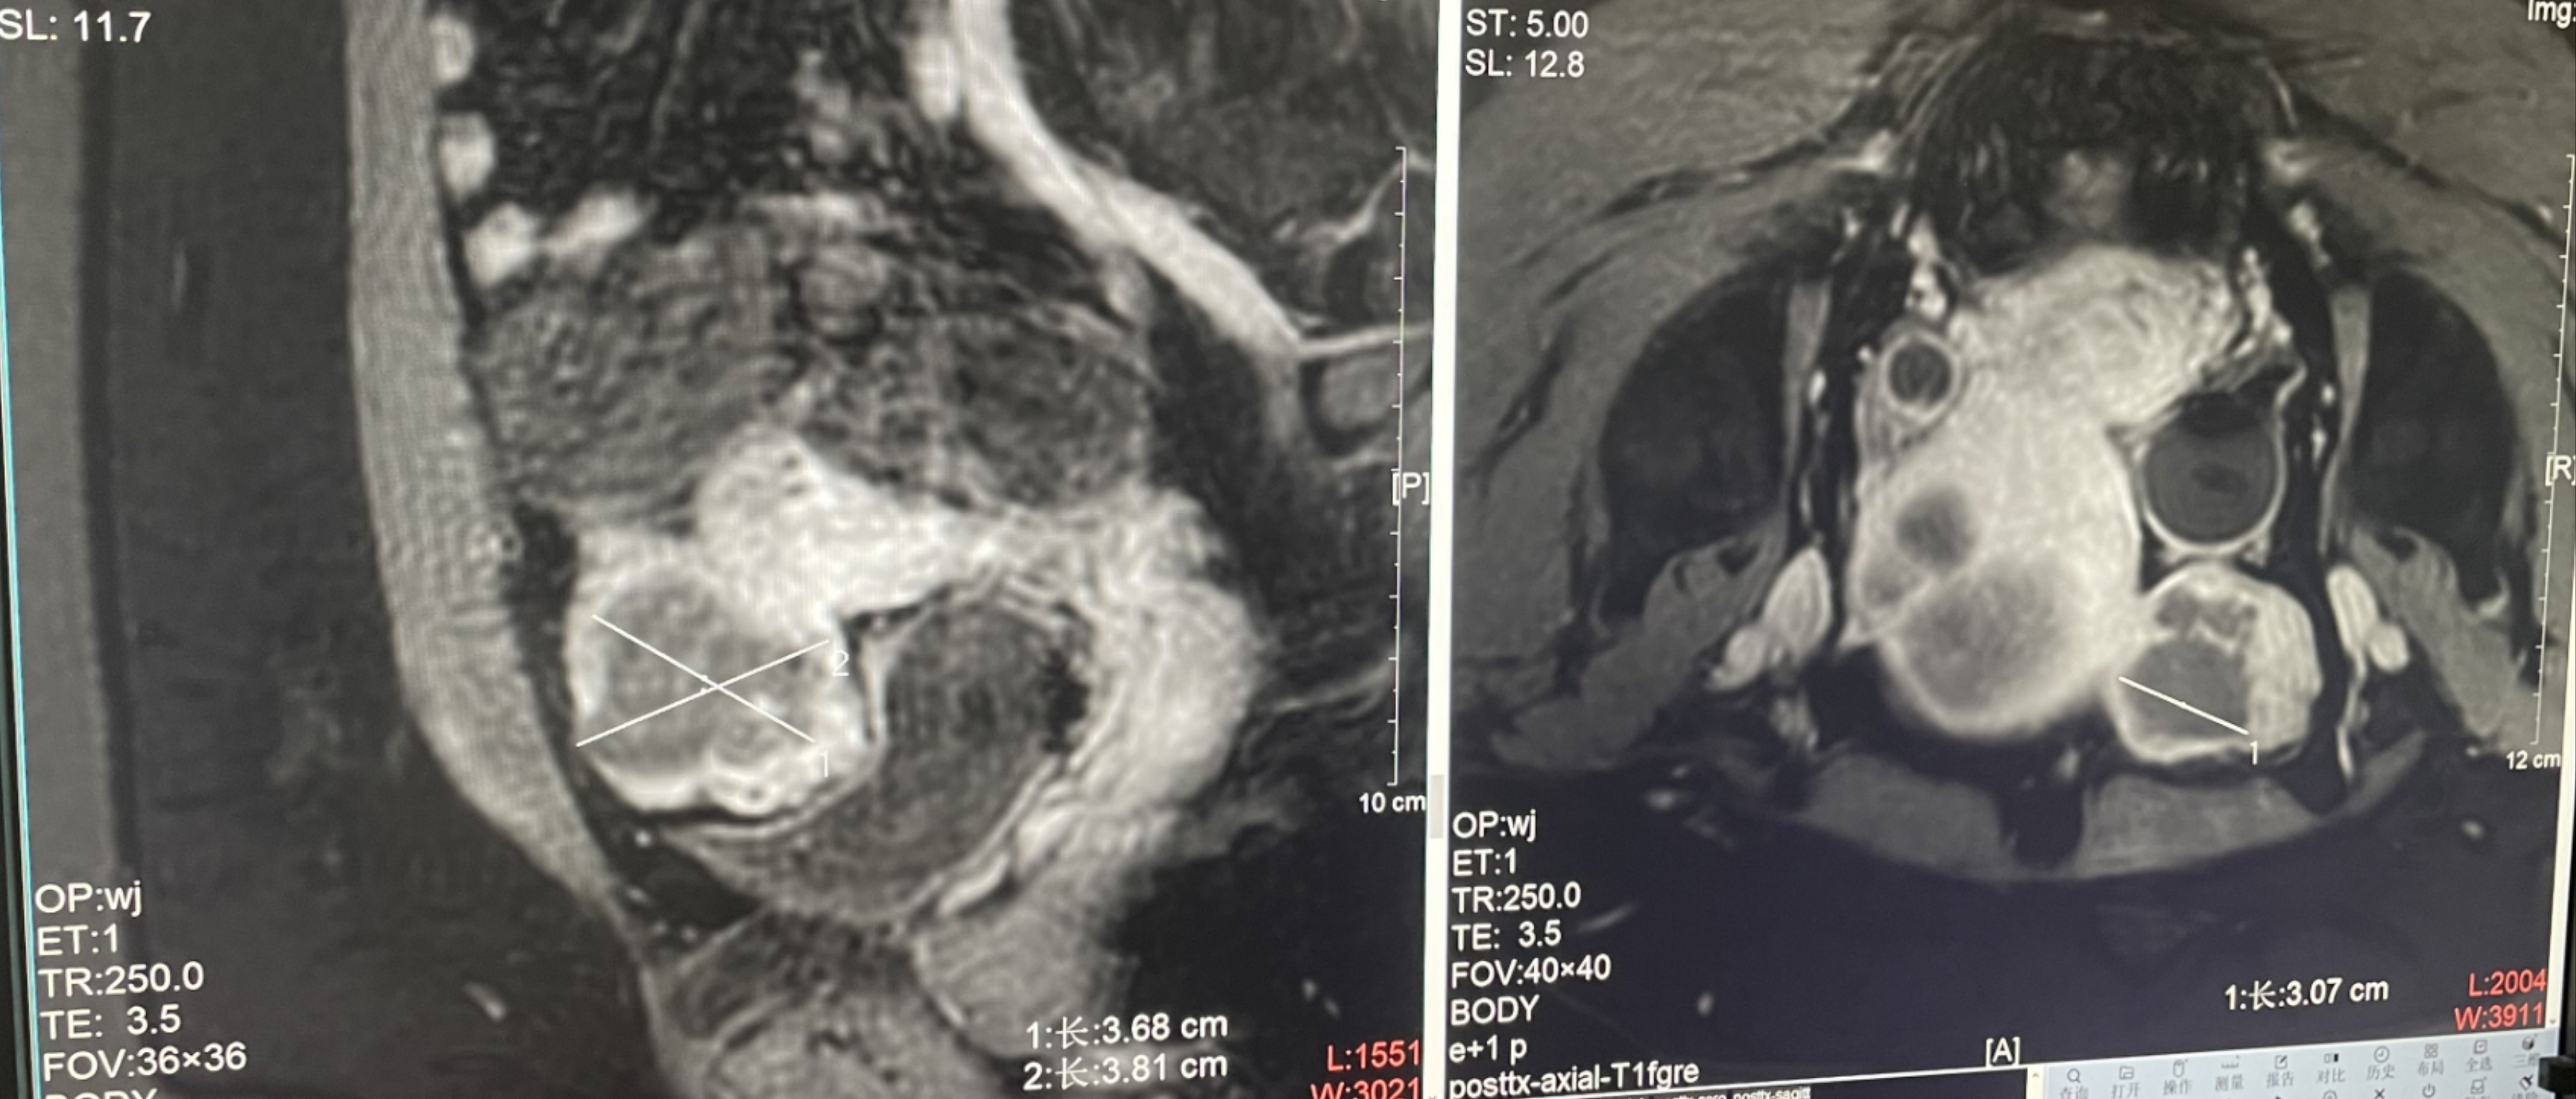

診斷:子宮肌瘤

腫瘤尺寸:約為45*52*38mm

ROT深度:腫瘤的ROT中心距離皮膚62mm

術(shù)后評估:術(shù)后造影增強圖像顯示消融區(qū)域(右側(cè))與腫瘤區(qū)域(左側(cè))重合度較好,非灌注區(qū)域連續(xù)且一致。

結(jié)論:對該腫瘤具有非常好的消融效果,治療過程中,溫度上升曲線符合預期,每個被治療的靶點240CEM區(qū)域體積較大、外形飽滿、連續(xù)。病灶消融良好,NPV體積比約88.7%。